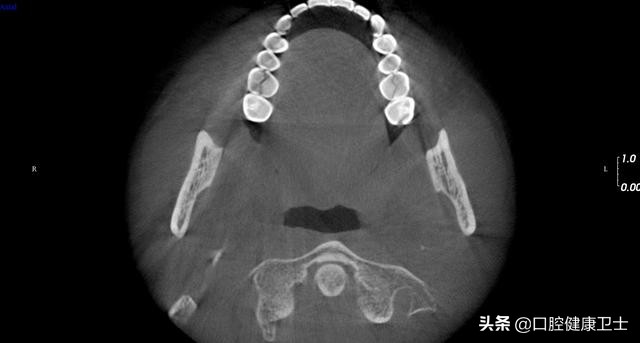

CT见,右上第一磨牙近远中向劈裂,左上第一磨牙也是近远中向劈裂,暂不处理。

CT见,右上第一磨牙劈裂至髓室,左上第一磨牙同样,暂不处理。

CT见,右上第一磨牙劈裂至髓室底,没有保留可能性,建议拔除。左上第一磨牙,暂不处理。